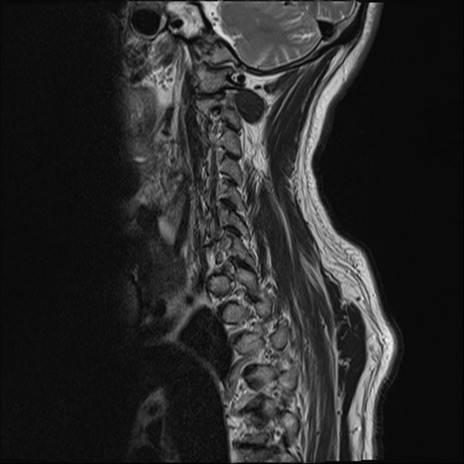

【整形】TIPS症例7 頚椎MRI T2WI(矢状断像)

頚椎MRI

T1WI(矢状断像)